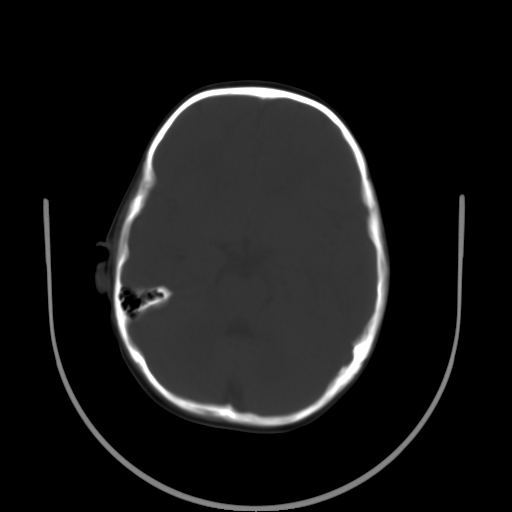

以下是引用深泽交通医院在2009-10-16 8:25:00的发言:[br]右眼环出血伴异物

以下是引用卜一在2009-10-16 15:01:00的发言:[br]右眼球挫裂伤伴异物!

以下是引用拾荒者在2009-10-17 18:38:00的发言:[br]鼻面部皮下积气,右侧睑缘及眼球壁高密度异物影,左侧眼球壁晶状体内侧缘处是圆形低密度影。低密度异物?应提请眼科医生注意。